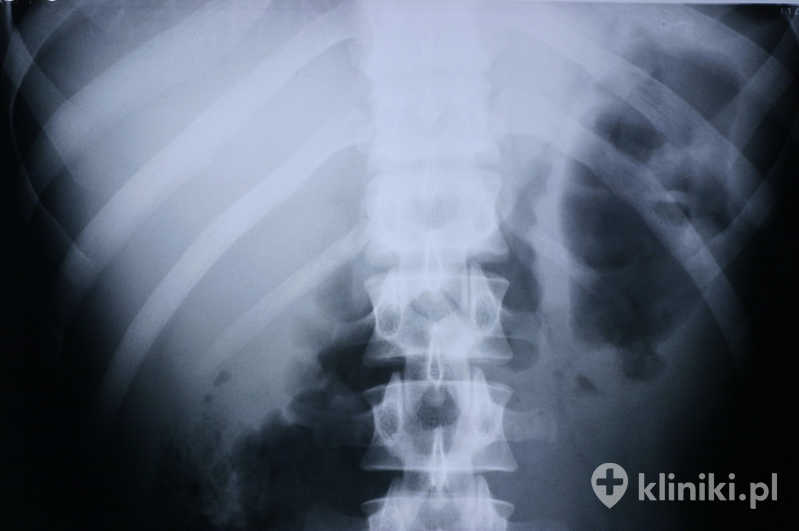

Jak rozpoznać złamanie kręgosłupa piersiowego lub lędźwiowego?

Złamanie kręgosłupa piersiowego lub lędźwiowego rozpoznaje się na podstawie diagnostyki obrazowej. W zależności od sytuacji klinicznej może ona obejmować RTG, tomografię komputerową oraz rezonans magnetyczny. Dopiero połączenie wyników niezbędnych w danym przypadku badań pozwala dokładnie ocenić zakres urazu i ustalić, z jakim rodzajem złamania mamy do czynienia. To właśnie ten etap decyduje o wyborze dalszego sposobu leczenia.